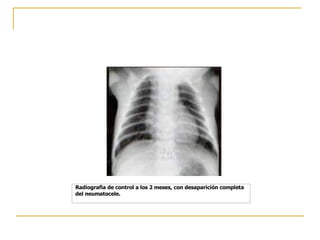

Radiografia de control a los 2 meses, con desaparición completa del neumatocele.

Radiografia de controla los 2 meses, con desaparición completa del neumatocele.